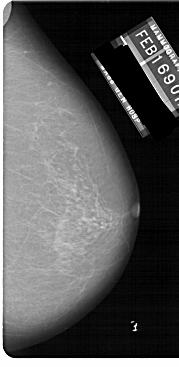

A_1149_1.LEFT_MLO

LEFT_MLO LINES 5491 PIXELS_PER_LINE 3031 BITS_PER_PIXEL 12 RESOLUTION 43.5 OVERLAY